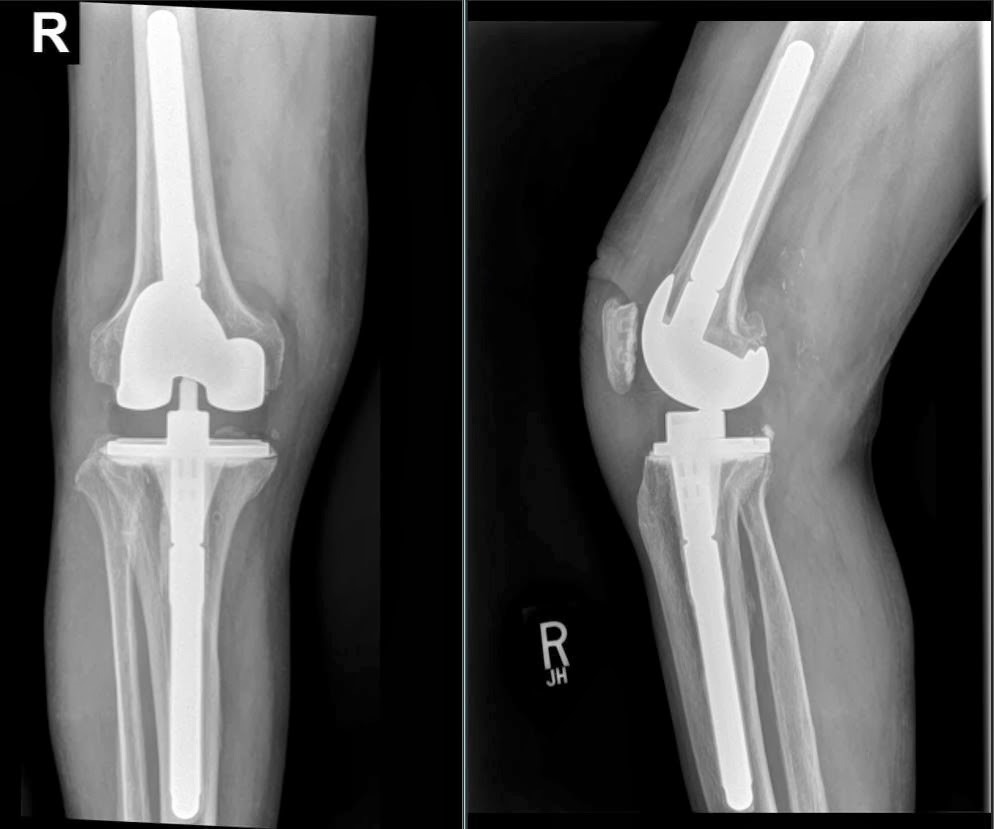

Вероника: Перед операцией, в июне, прошла 4 курса химиотерапии, чтобы уменьшилась опухоль. На август назначили операцию. У меня был поражен небольшой участок ноги, но требовалось удалить коленную чашечку и часть бедра. Мне предложили эндопротез, который позволял сохранить конечность и вести нормальную жизнь.

Справка: Эндопротезирование – вариант органосохраняющего лечения, при котором удаляется пораженная кость с опухолью, а на ее место устанавливается эндопротез (искусственный мегапротез или имплант). Таким образом, собственная конечность и ее функция сохраняются.

Вероника: После рака ты хочешь забыть о болезни, но не получается. Это мешает по жизни. Например, мне нельзя долго находиться на солнце. То есть уже не съездить отдохнуть на море. Протез тоже вносит определенные ограничения, поскольку сгиб колена должен составлять 90 градусов и не более. Нельзя допускать падения, за семь лет, наверное, два раза всего упала, старалась настолько аккуратно ходить. Невозможно кататься на велосипеде, нельзя кататься на лыжах, коньках и роликах, в фитнес-зале разрешено делать не все упражнения. Пришлось со всем этим распрощаться, физическая активность стала очень ограниченной. До болезни я хотела заниматься танцами, а теперь это невозможно. Всё перевернулось. Ограничения есть, но зато я жива, и нога сохранена. Друзья и близкие относятся с пониманием, оберегают меня.

Вероника: После операции мониторинг был строгий и частый. Сейчас раз в год приезжаю к НМИЦ к лечащему врачу ‒ Светлане Александровне Кулевой. Также прохожу комплексное обследование: рентген ноги, УЗИ брюшной полости, анализы.